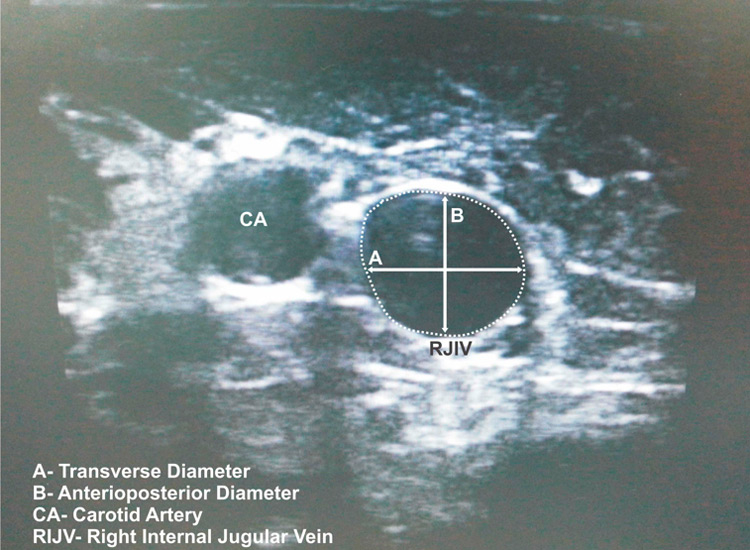

Figure 1

A still image of the RIJV, diameters and cross-sectional area.

Three sets of images taken from every patient were evaluated by an anaesthetist who was not aware which group of ventilation mode the image belonged to. The CSA, transverse and anteroposterior diameters were measured using the built-in software of the ultrasound. Anteroposterior diameter is the distance between the anterior and the posterior wall of the RIJV. Transverse diameter is the distance between the medial and lateral wall of the RIJV (fig. 1).